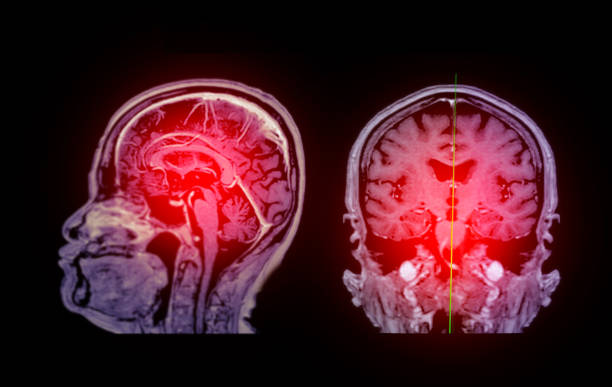

缺血性腦卒中,又稱腦梗死,是一種因腦部血液循環障礙導致的腦組織壞死疾病。它給患者帶來的不僅是身體上的痛苦,更是心理上的巨大壓力。